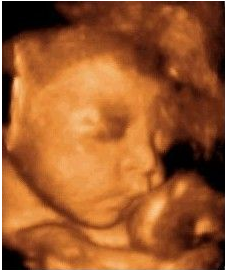

可是寶寶似乎不怎么配合我們,舉著小手擋在臉前,還留給了我們一個(gè)美麗的側(cè)臉,這是猶抱琵琶半遮面的節(jié)奏么?看來(lái)我家小寶貝兒是個(gè)害羞的娃呀。我跟寶寶輕輕說(shuō)著話,叫它乖寶寶,可是寶寶還是一副我不理你的樣子,這時(shí)醫(yī)生用手輕輕捏了下我的肚子,寶寶這才把臉轉(zhuǎn)了過(guò)來(lái),我終于看到寶寶的正面了,簡(jiǎn)直是和它媽媽一樣美呆了,嘻嘻。

醫(yī)生一邊給醫(yī)生助理報(bào)數(shù)據(jù),一邊耐心的為我講解,哪里是寶寶的手啊腳啊,之后我們又聽(tīng)到了臍血流和胎心音,醫(yī)生說(shuō)寶寶的身體很健康,一切都正常,我這才放心下來(lái)。整個(gè)四維彩超檢查過(guò)程大約持續(xù)1個(gè)小時(shí),可我仍覺(jué)得意猶未盡,期間還把寶寶的萌照拍了下來(lái),是不是很可愛(ài)呢?